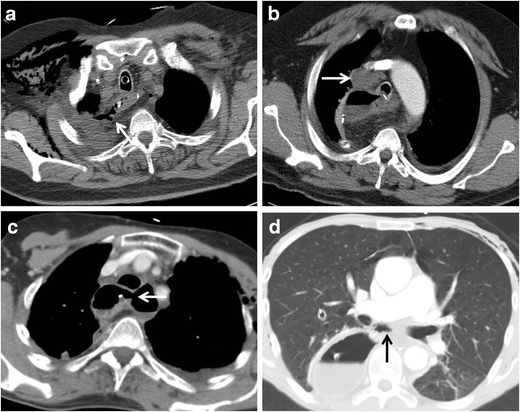

Fig. 3

figure 3

Examples of CT findings associated with the presence of anastomotic leakage after esophagectomy. A: Image shows a fistula between the gastric tube and right pleural cavity (arrow). B: Image shows a fluid collection (arrow) in the mediastinum. C: Image shows a visible discontinuity of the esophagogastric wall (arrow). D: Image shows a mediastinal air cavity (arrow) after esophagectomy